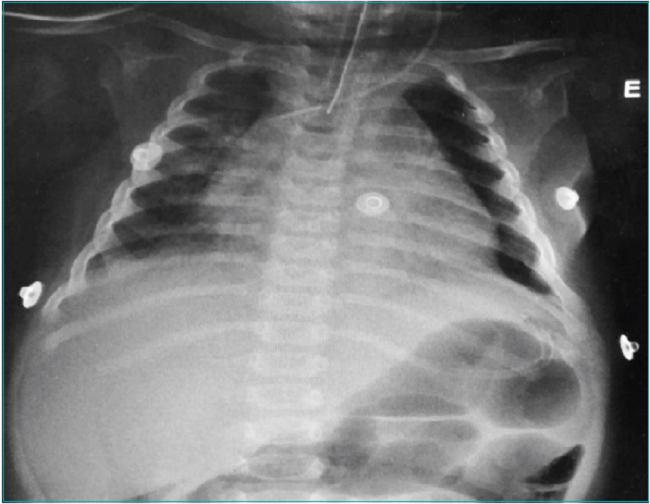

Lactente de seis meses de idade, do sexo feminino, previamente saudável, foi encaminhada à Unidade de Terapia Intensiva Pediátrica do Hospital das Clínicas da Universidade de Campinas (HC-UNICAMP) por coma. Quinze dias antes do coma, a paciente apresentou sintomas respiratórios e recebeu antipiréticos e beta-2 agonistas de curta duração. Quatro dias antes do coma, apresentou desconforto respiratório e febre, sendo então internada em um hospital secundário na região metropolitana de Campinas, São Paulo. No primeiro dia de internação, apresentava febre persistente e taquicardia sinusal. Radiografia do tórax revelou um aumento da área cardíaca sem alterações radiográficas nos pulmões (Figura 1). No dia seguinte, um ecocardiograma mostrou espessamento pericárdico com derrame volumoso e sinais de tamponamento cardíaco. Foi relatado que a paciente estava em bom estado geral. No terceiro dia de internação apresentou crises convulsivas. Foram administrados diazepam, fenobarbital e fenitoína, e solicitou-se transferência urgente para a unidade de terapia intensiva. Durante o transporte, a paciente foi intubada e recebeu dobutamina. Ao chegar ao HC-UNICAMP, evoluiu com choque hipotensivo, e apresentava 3 pontos na escala de coma de Glasgow.